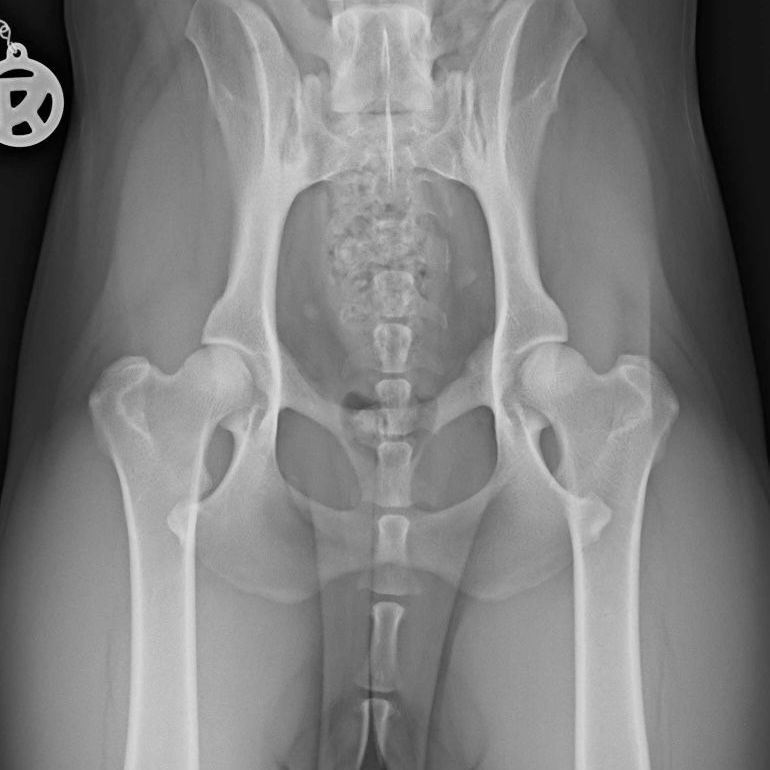

Ein Bandscheibenvorfall beim Hund tritt auf, wenn der gelartige Kern einer Bandscheibe aus dem Faserring austritt, das Rückenmark komprimiert oder sogar verletzt und/ oder auf umgebenden Nerven drückt.

Wenn ein Bandscheibenvorfall vermutet wird, ist es für den späteren Behandlungserfolg maßgeblich, dass der Hund schnellstmöglich einem Tierarzt/ bei einer Tierklinik vorgestellt wird. Sollte eine OP notwendig sein, um schnellstmöglich den Druck vom Rückenmark zu nehmen und weitere Schäden zu vermeiden, dann ist der größte Genesungserfolg bei einer OP innerhalb der ersten 24 Stunden zu erwarten.